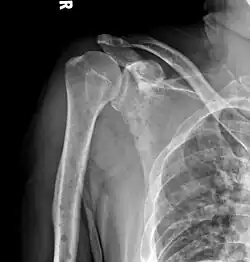

The diagnostic examination of a person with suspected multiple myeloma typically includes a skeletal survey. This is a series of X-rays of the skull, axial skeleton, and proximal long bones. Myeloma activity sometimes appears as "lytic lesions" (with local disappearance of normal bone due to resorption) or as "punched-out lesions" on the skull X-ray ("raindrop skull"). Lesions may also be sclerotic, which is seen as radiodense.[76] Overall, the radiodensity of myeloma is between −30 and 120 Hounsfield units (HU).[77] Magnetic resonance imaging is more sensitive than simple X-rays in the detection of lytic lesions. An MRI may supersede a skeletal survey, especially when vertebral disease is suspected. Occasionally, a CT scan is performed to measure the size of soft-tissue plasmacytomas. Nuclear Medicine Bone scans are typically not of any additional value in the workup of people with myeloma (no new bone formation; lytic lesions not well visualized on nuclear bone scan).

-

X-ray of the forearm, with lytic lesions -

Skull X-ray showing multiple lucencies due to multiple myeloma -

Multiple myeloma in the upper arm -

Pathological fracture of the lumbar spine due to multiple myeloma -